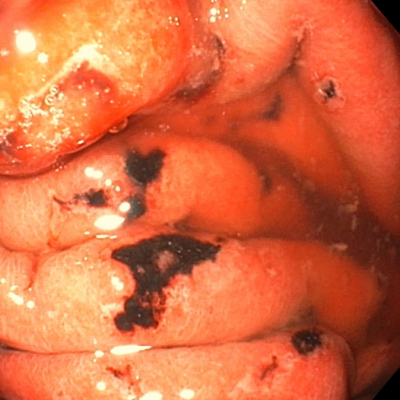

| ڈoŒŒگ«ˆف‰ٹ | |

|